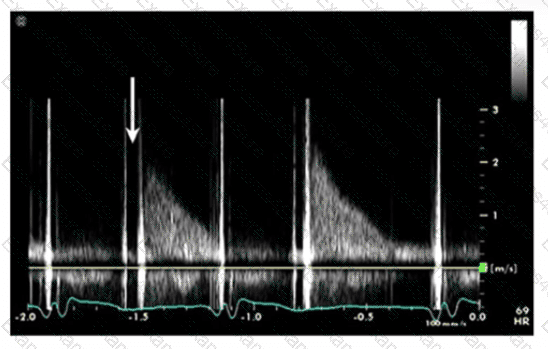

The sonographer obtains this Doppler signal while using the non-imaging transducer in the apical position. What is the best way to differentiate between mitral regurgitation and aortic stenosis signals in the waveform shown in this image?